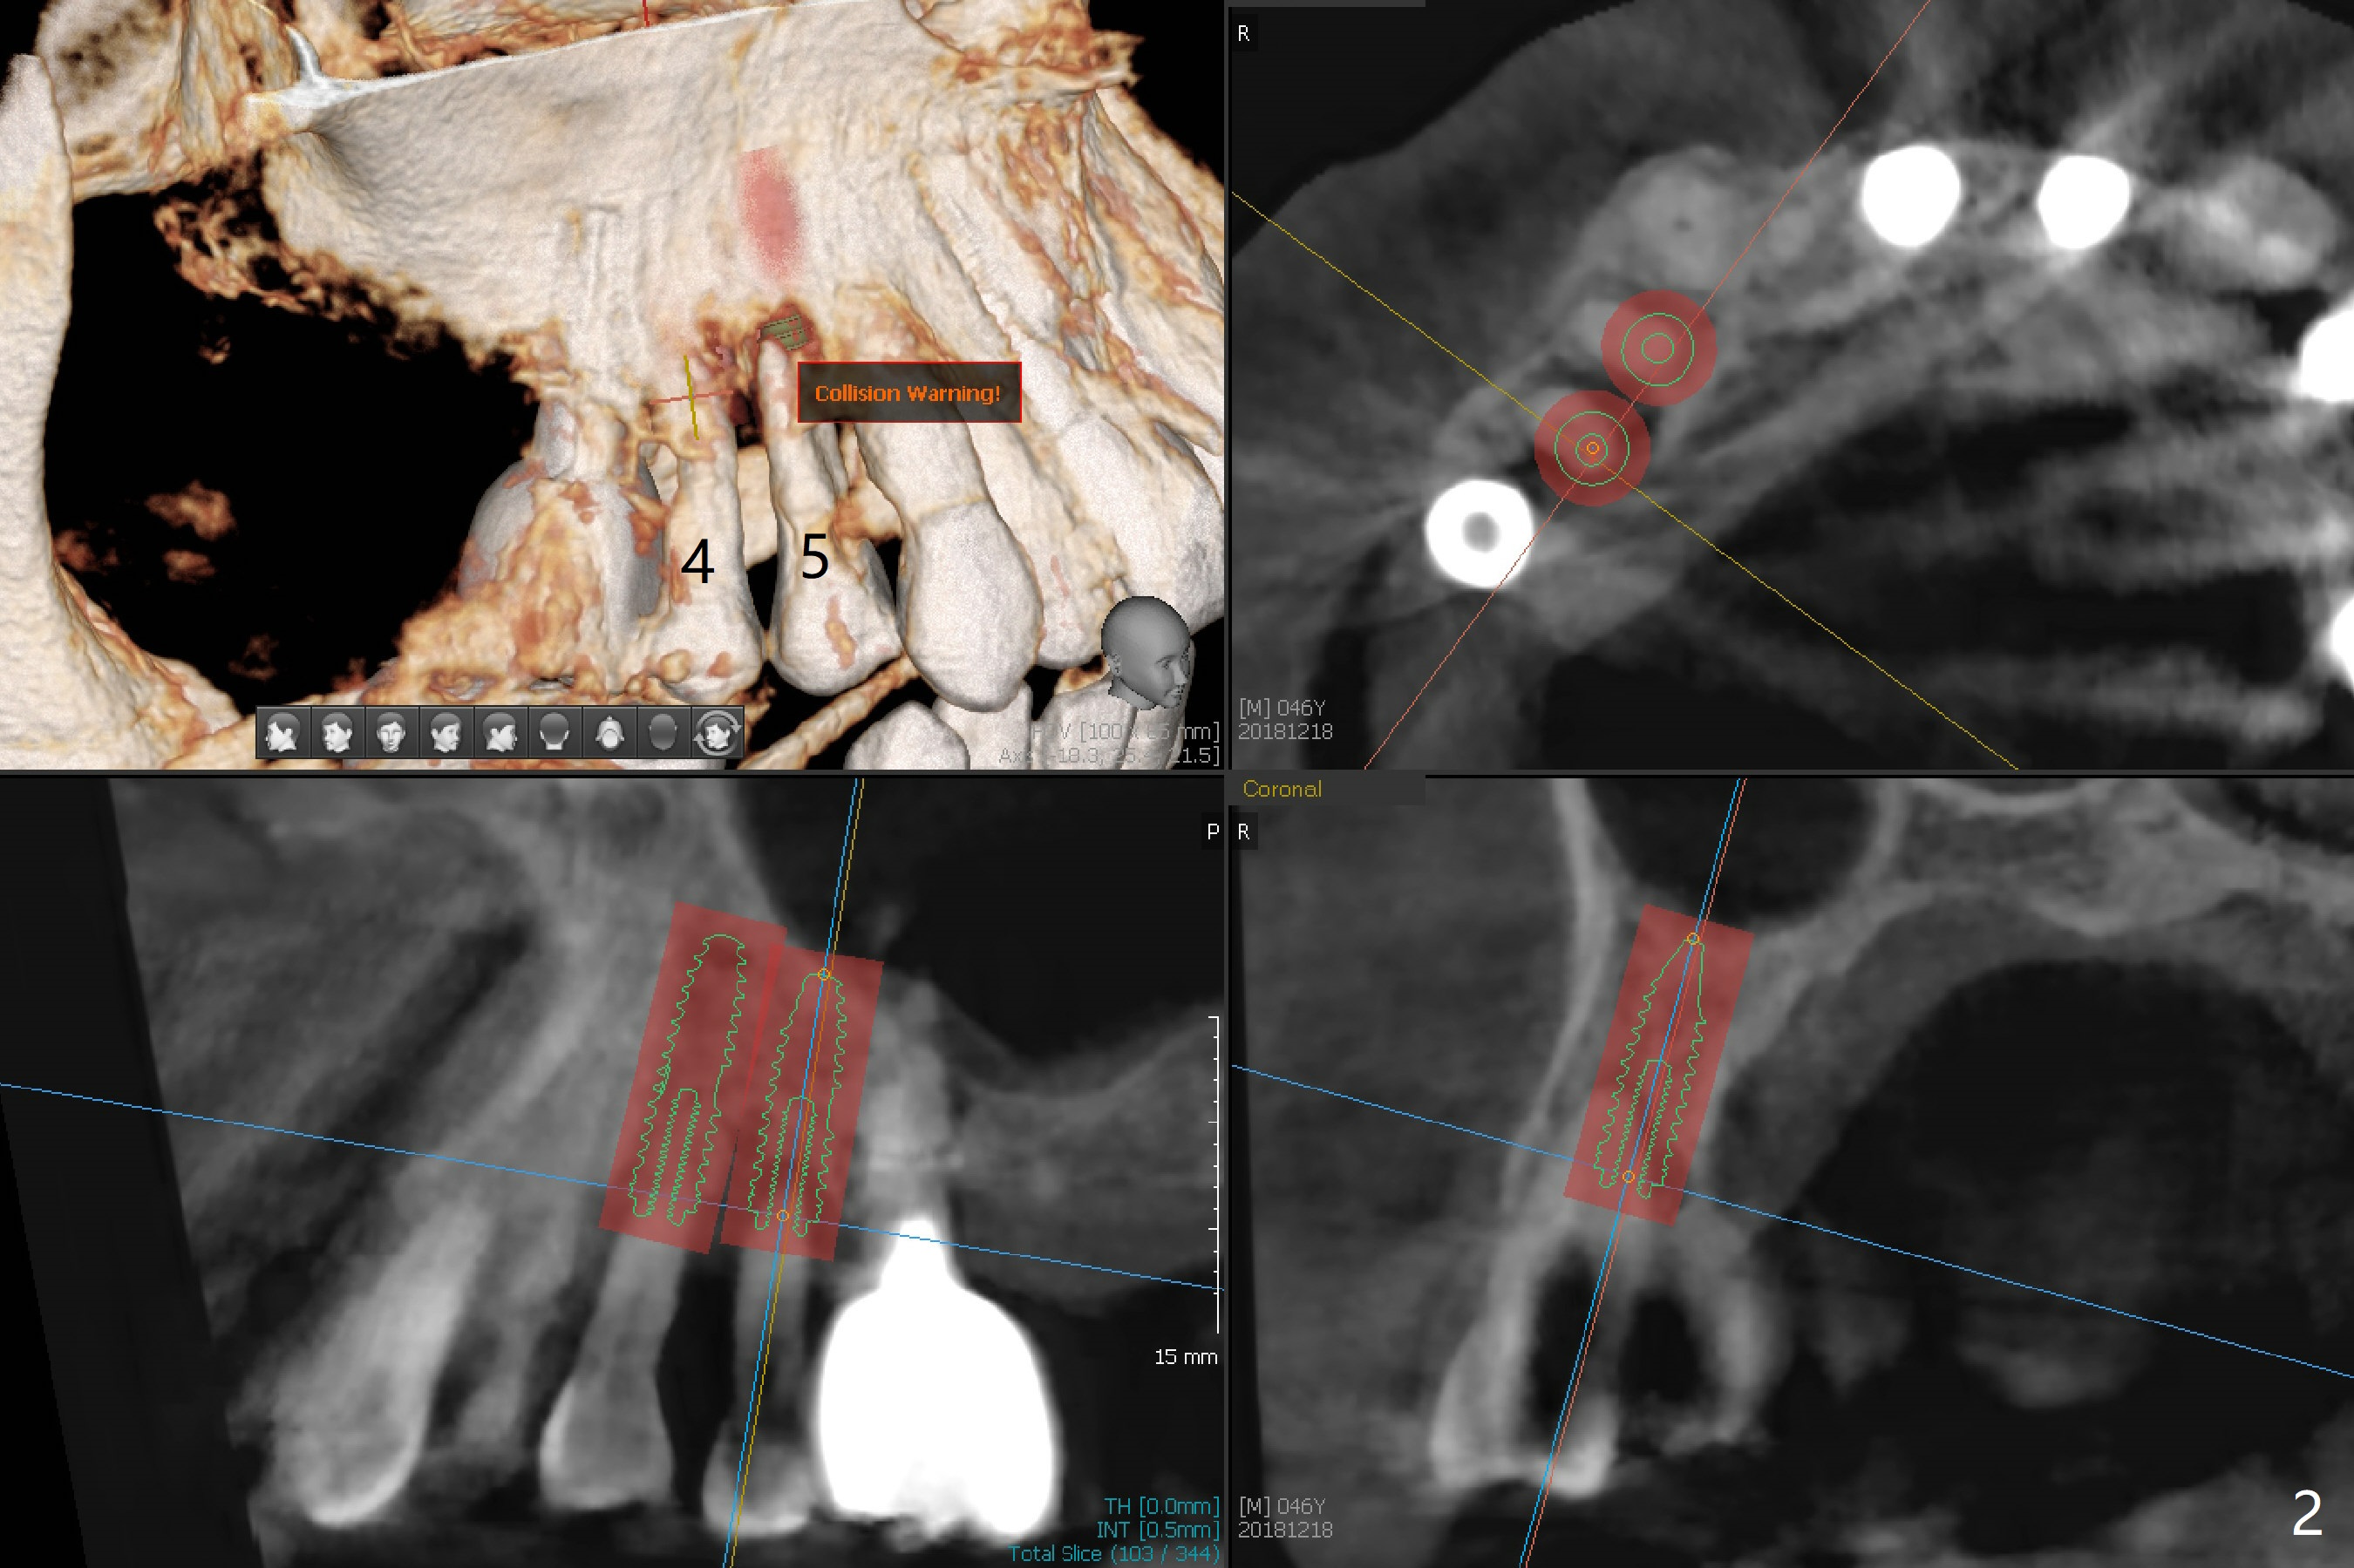

A 46-year-old man requests immediate implants at #4 and 5 because of pain associated with advanced periodontitis. Implants at #15 and 29 were removed with bone graft 4 months earlier (Fig.1). All of the 4 implants will be placed with guide. When 3.5 mm implants are placed at #4 and 5, they appear to be too close to each other (Fig.2). It is alright when the diameter changes to 3.0 mm (Fig.3). While a 5x10 mm implant will be placed at the 2nd stage (Fig.4), a 4x11.5 mm one will be placed in the same appointment as #4 and 5 (Fig.5).